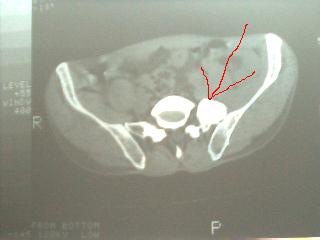

以下是引用子期在2006-12-6 13:02:00的发言:[br]考虑腰5左横突骨软骨瘤.

以下是引用卜一在2006-12-6 13:06:00的发言:[br]支持:腰5左侧横突肥大

以下是引用程军建在2006-12-6 15:15:00的发言:[br]同意:腰5左侧横突肥大

以下是引用jinguoji在2006-12-6 15:11:00的发言:[br]腰5左侧横突肥大.